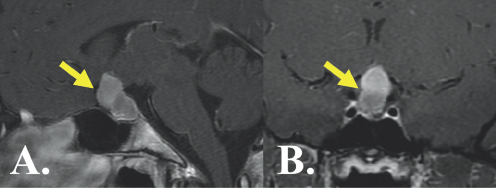

The tunnel vision progressed to blurriness that Arianna became more aware of. As James recalls, “Things got to the point where I would have to stand right in front of her just to get her to notice me.” At a check-up with her optometrist, serious abnormalities in both visual fields and acuity were noted. Arianna was immediately referred to a neuro-ophthalmogist, where Humphrey visual fields confirmed progressive visual loss in the outer half of both eyes consistent with bitemporal hemianopsia (Figure 7.1).5 An MRI scan of the brain was subsequently ordered. The MRI demonstrated an enhancing lesion involving the sellar and suprasellar regions with severe associated compression of the optic nerves and chiasm (Figure 7.2). The radiographic features of the tumor were most consistent with a craniopharyngioma.

(Left) A yellow arrow points to a light gray blob in the center of the image. It is surrounded by black and gray color variations depicting brain structures. (Right) A yellow arrow points to a light gray blob in the center of the image. It is surrounded by black and gray color variations depicting brain structures.

FIGURE 7.2 MRI of a Complex Craniopharyngioma of the Brain. Pre-operative MRI demonstrates a craniopharyngioma (yellow arrows) resulting in severe compression of important brain structures required for vision.